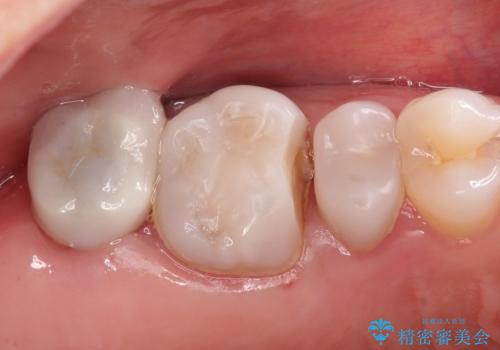

笑った時に見える金属を白くしたい

目立つ銀歯を白くしたい 奥歯のセラミック治療